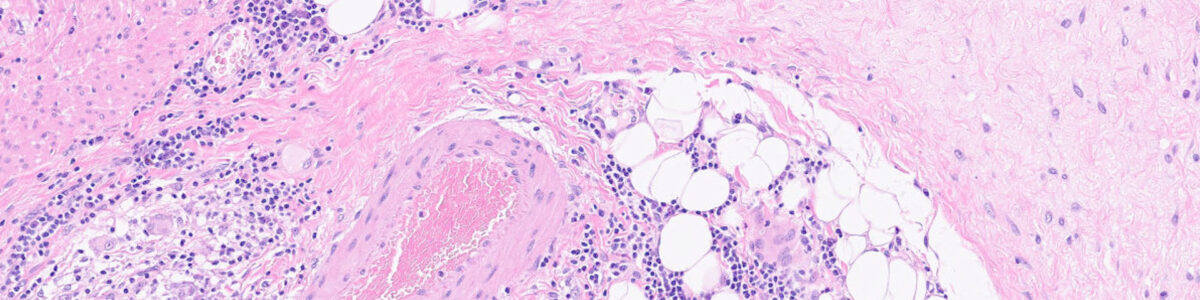

Denne dag sætter fokus på hele processen omkring vævspræparering og vigtigheden af god kvalitet. Vi gennemgår centrale trin fra udskæring til indstøbning, og ser på, hvordan man kan reducere fejl gennem forbedrede arbejdsgange.

Deltagerne inviteres til at dele erfaringer fra laboratoriet indenforsporbarhed og vævspræparering, som styrker kvalitet og sikkerhed gennem hele processen.